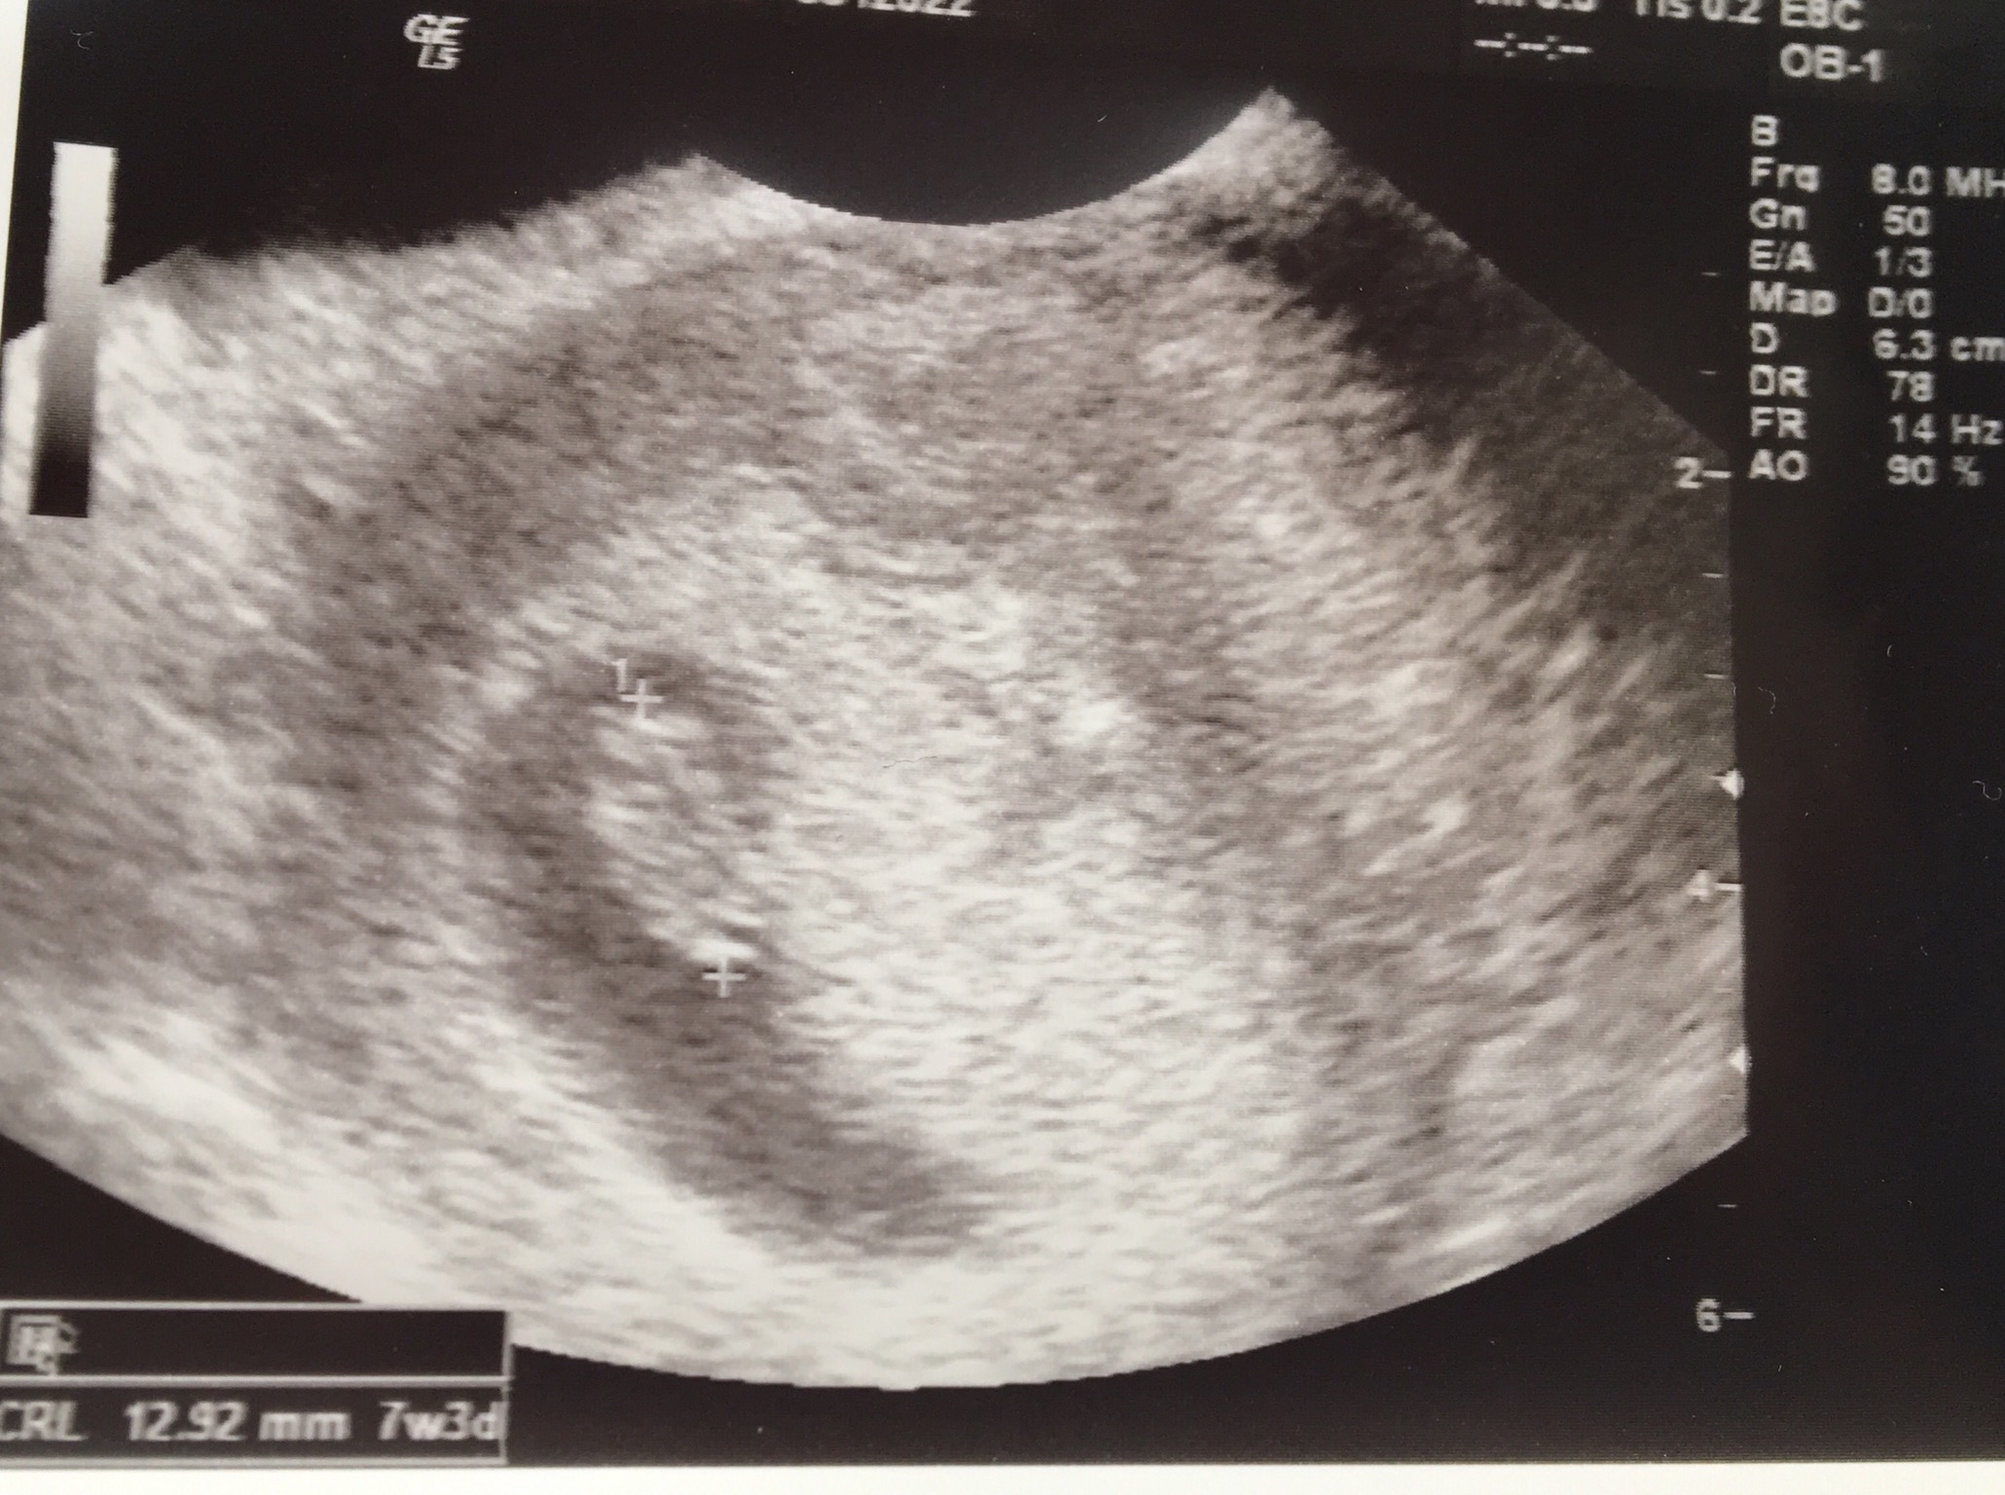

New here, but I got to see this little nugget a few days ago. Measured 7+4 which moved my due date from 8/15 to 7/26 (obviously what I thought was a period in November was not )